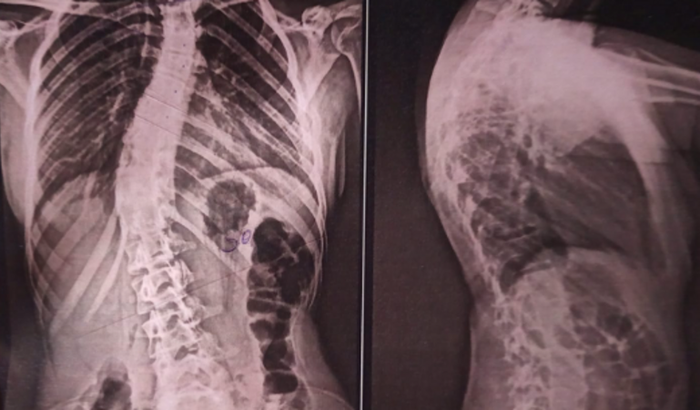

Eu tenho escoliose congênita que é um desviu na coluna, a minha é em “S” a acentuação da curva de lordose lombar esta em 45.5 graus.